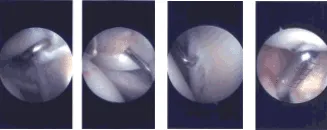

El implante bioinductivo se insertó a través de la puerta lateral hacia la articulación. Se creó un portal superior para la inserción de chinchetas. Las tachuelas se insertaron a través del portal superior y el implante bioinductivo se fijó en el manguito rotador usando tachuelas de PLA x7. Al encontrarla en una posición y fijación satisfactorias, se tomaron y guardaron las fotos finales.

Imágenes de artroscopia intraoperatoria